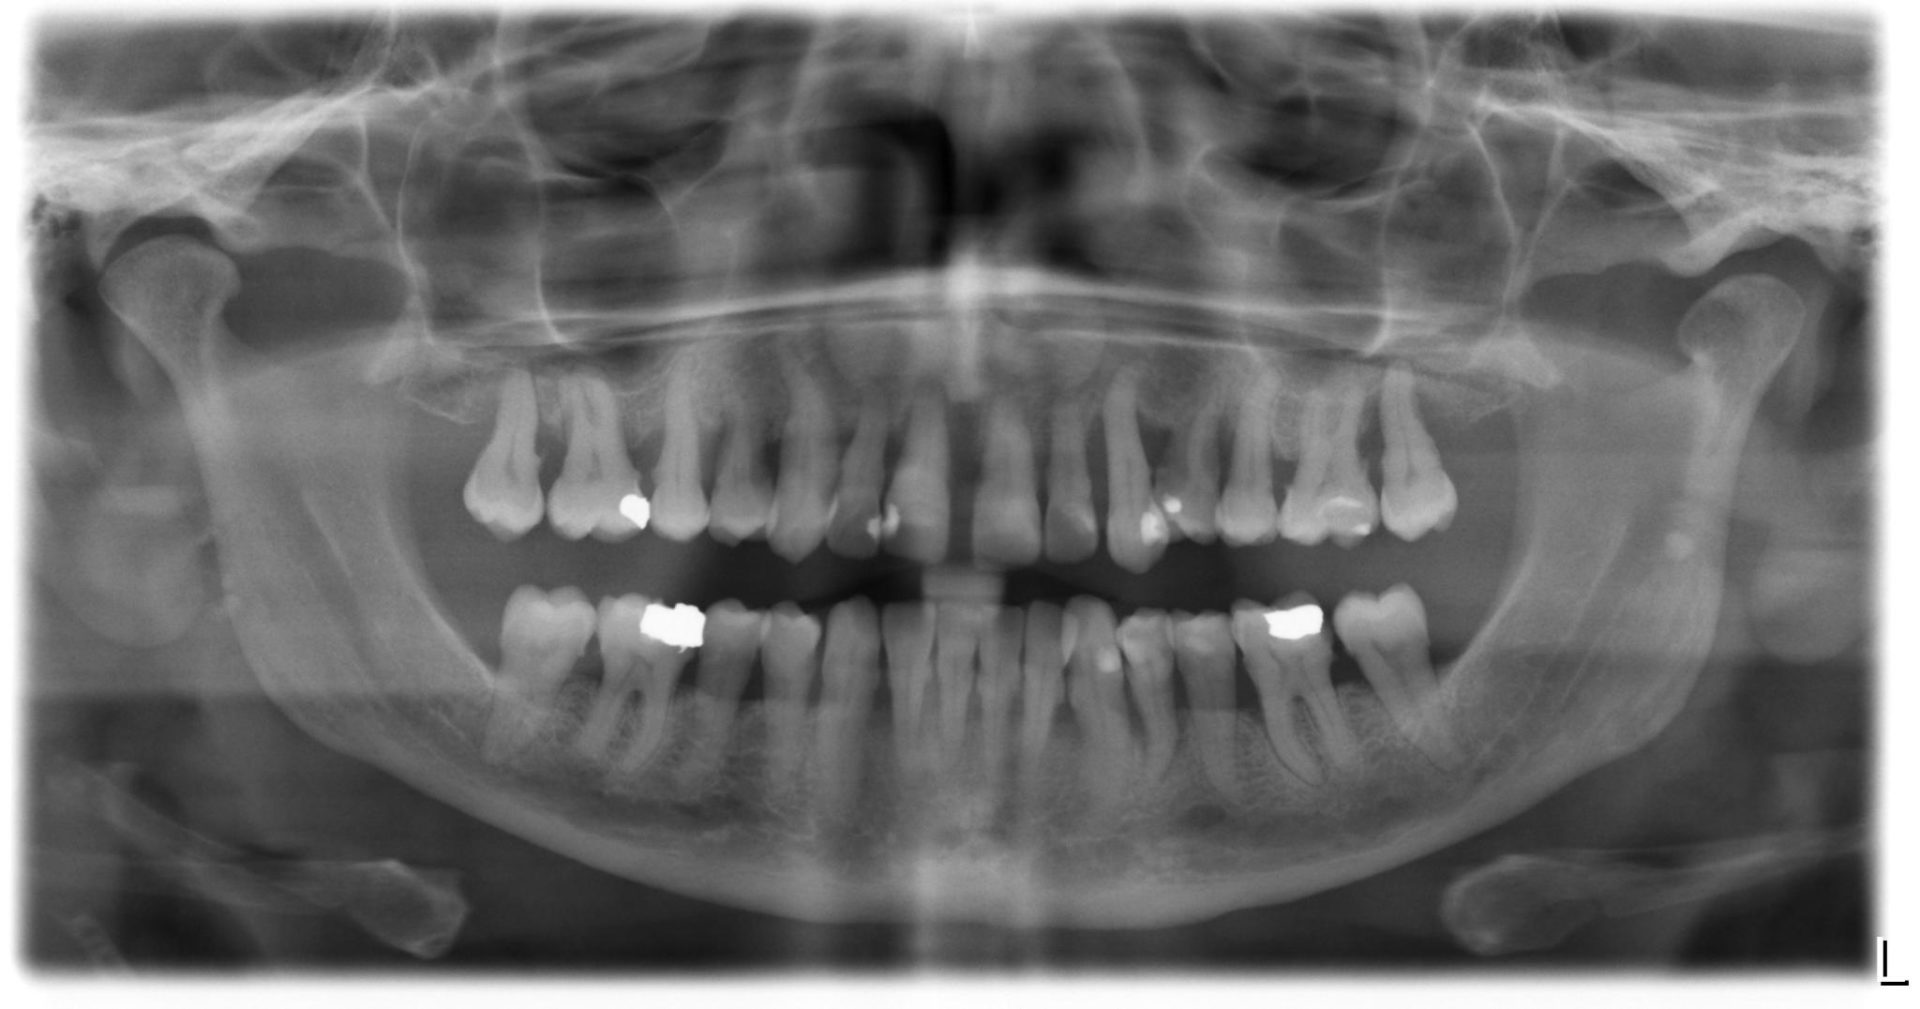

Parodontie Sévère

Grosse perte osseuse visible sur

la radio   on pourrait avec un stylet marquer en 2 couleurs le niveau osseux

actuel et normal

fin de traitement paro